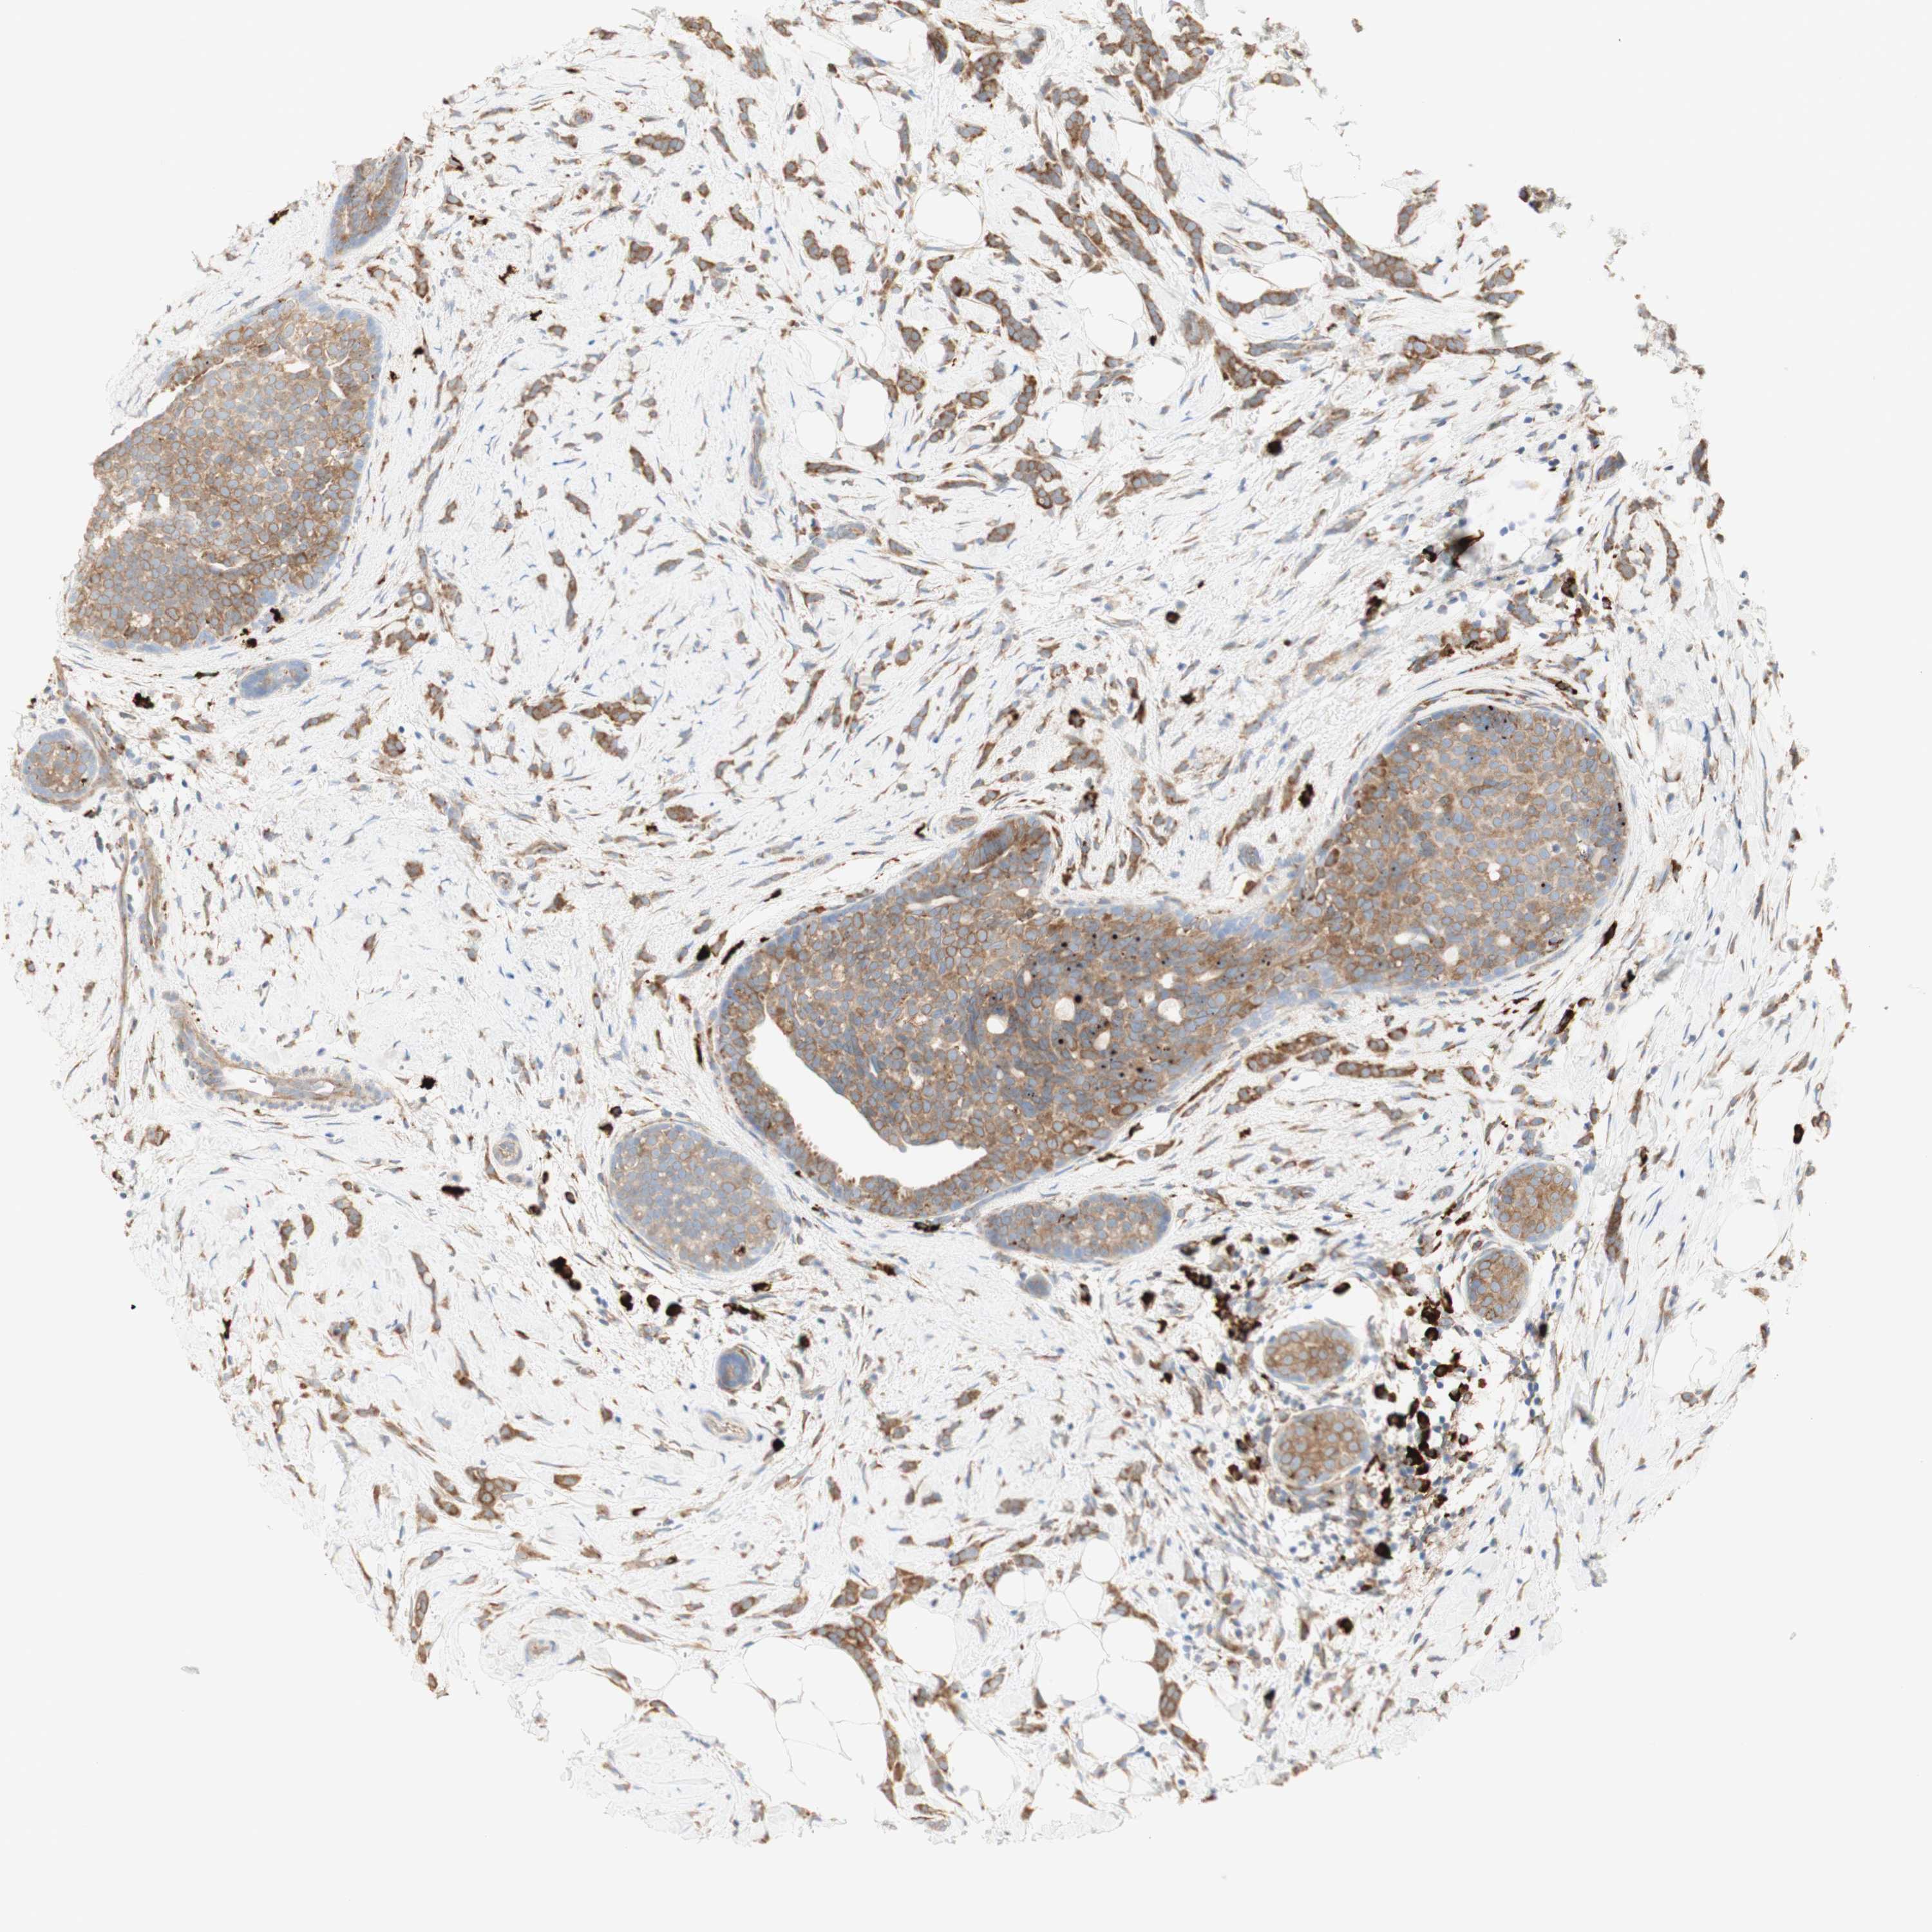

CANCER BREAST CANCER Show tissue menu

BRCA TCGA BRCA VALIDATION PROTEIN EXPRESSION

ANTIBODIES

AND

VALIDATION